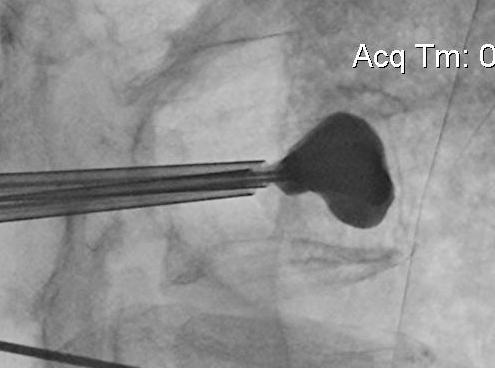

Technique

Insert a balloon first and inflate

- bilaterally into each pedicle

- will restore some anatomy

- then inject PMMA